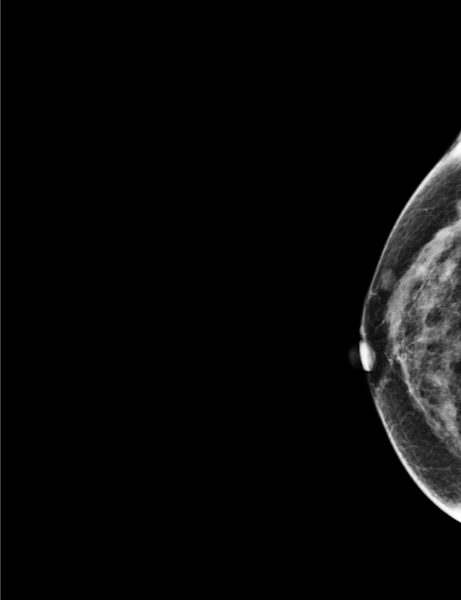

During the screening, two masses were found, one on the right breast (2cm DTN) and the other on the left breast (A1 cm DTN), categorized as suspicious.

The patient was called back for an ultrasound. The following biopsy performed showed lobular cancer infiltrating the left breast (two masses).

MammoScreen indicates one of the suspicious masses on the left breast in score 8 on tomosynthesis.